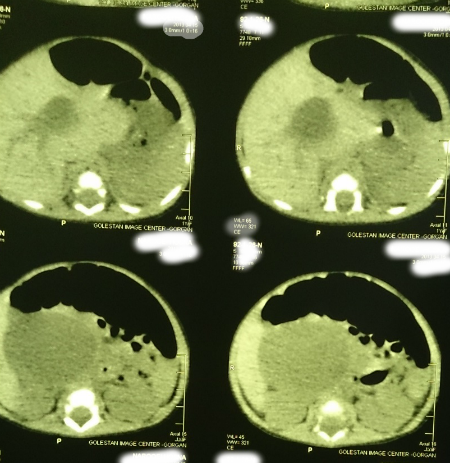

A 22-day-old female infant was admitted due to prolonged jaundice. She was icteric from the fourth day of life along with acholic stools and abdominal distension. Direct hyperbilirubinemia was detected in blood tests. Her total bilirubin and direct bilirubin were 19mg/dl and 10.3mg/dl respectively. Clotting profile was normal. Liver function tests (LFTs) were AST (84IU/L), ALT (81IU/L), and Alkaline phosphate (2024 IU/L). The abdominal sonography showed a choledochal cyst (56x43x46mm) with few echogenic areas in it. Wall thickness and echogenicity of gallbladder as well as intra hepatic ducts were normal. Abdominal CT scan confirmed the existence of choledochal cyst (Fig. 1). The patient was operated after optimization. Operative findings included an extra hepatic choledochal cyst (type I) which was ending blind on either sides. Porta-hepatis showed type III biliary atresia. The choledochal cyst and gallbladder had no bile but mucinous secretions which were aspirated. The gallbladder and choledochal cyst were resected; the porta-hepatis dissected and Roux-en-y porto-enterostomy was performed. The wedge biopsies from porta-hepatis showed biliary atresia as donated by diffused feathery degeneration, cholestasis, pseudoacinar transformation, focal giant cell, bile duct proliferation, and fibrotic tissue. The histopathology of choledochal cyst showed a biliary epithelial lining and that of gallbladder showed congestion and near total obliteration. Postoperatively, the jaundice improved and the patient passed pigmented stool. Patient was allowed orally and discharged on short course of prednisolone, fat soluble vitamins and prophylactic antibiotic. At present, the infant is 10- months old and thriving well. The last total bilirubin is less than 1.5mg/dl.

Figure 1: Cyst at porta-hepatis. |